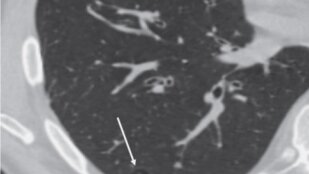

Bulla

Воздушная полость размером более 1 см (обычно несколько сантиметров) с четко очерченной тонкой стенкой. Толщина стенки буллы обычно не более 1 мм. Является одной из форм эмфиземы легких. Булла часто сочетается с другими эмфизематозными изменениями в прилегающей легочной паренхиме (см. Эмфизема буллезная).

На рентгенограммах иногда может выглядеть как полость округлой формы с тонкими стенками. Обычно это крупные полости, видимые стенки которых расположены перпендикулярно к плоскости приемника излучения...